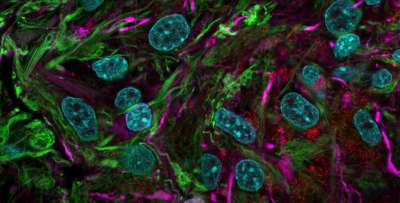

23.10.2021 Des "mini-cerveaux" cultivés en laboratoire révèlent des possibilités de traitement des maladies neurodégénératives  |

21.08.2021 Des organoïdes cérébraux humains cultivés en laboratoire ont des structures oculaires percevant la lumière  |